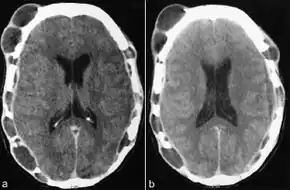

Tests usually include imaging using MRI.[5] Findings include breakdown of bone and thickening of the pituitary stalk. The perivascular space may appear prominent, the pituitary gland cystic and there may be signs in the white matter, a mass in the hypothalamus and enhancement of the meninges.[5]

MRI and CT scan findings in a mummy have revealed evidence of the disease dating back to 900-790. B.C.[17]